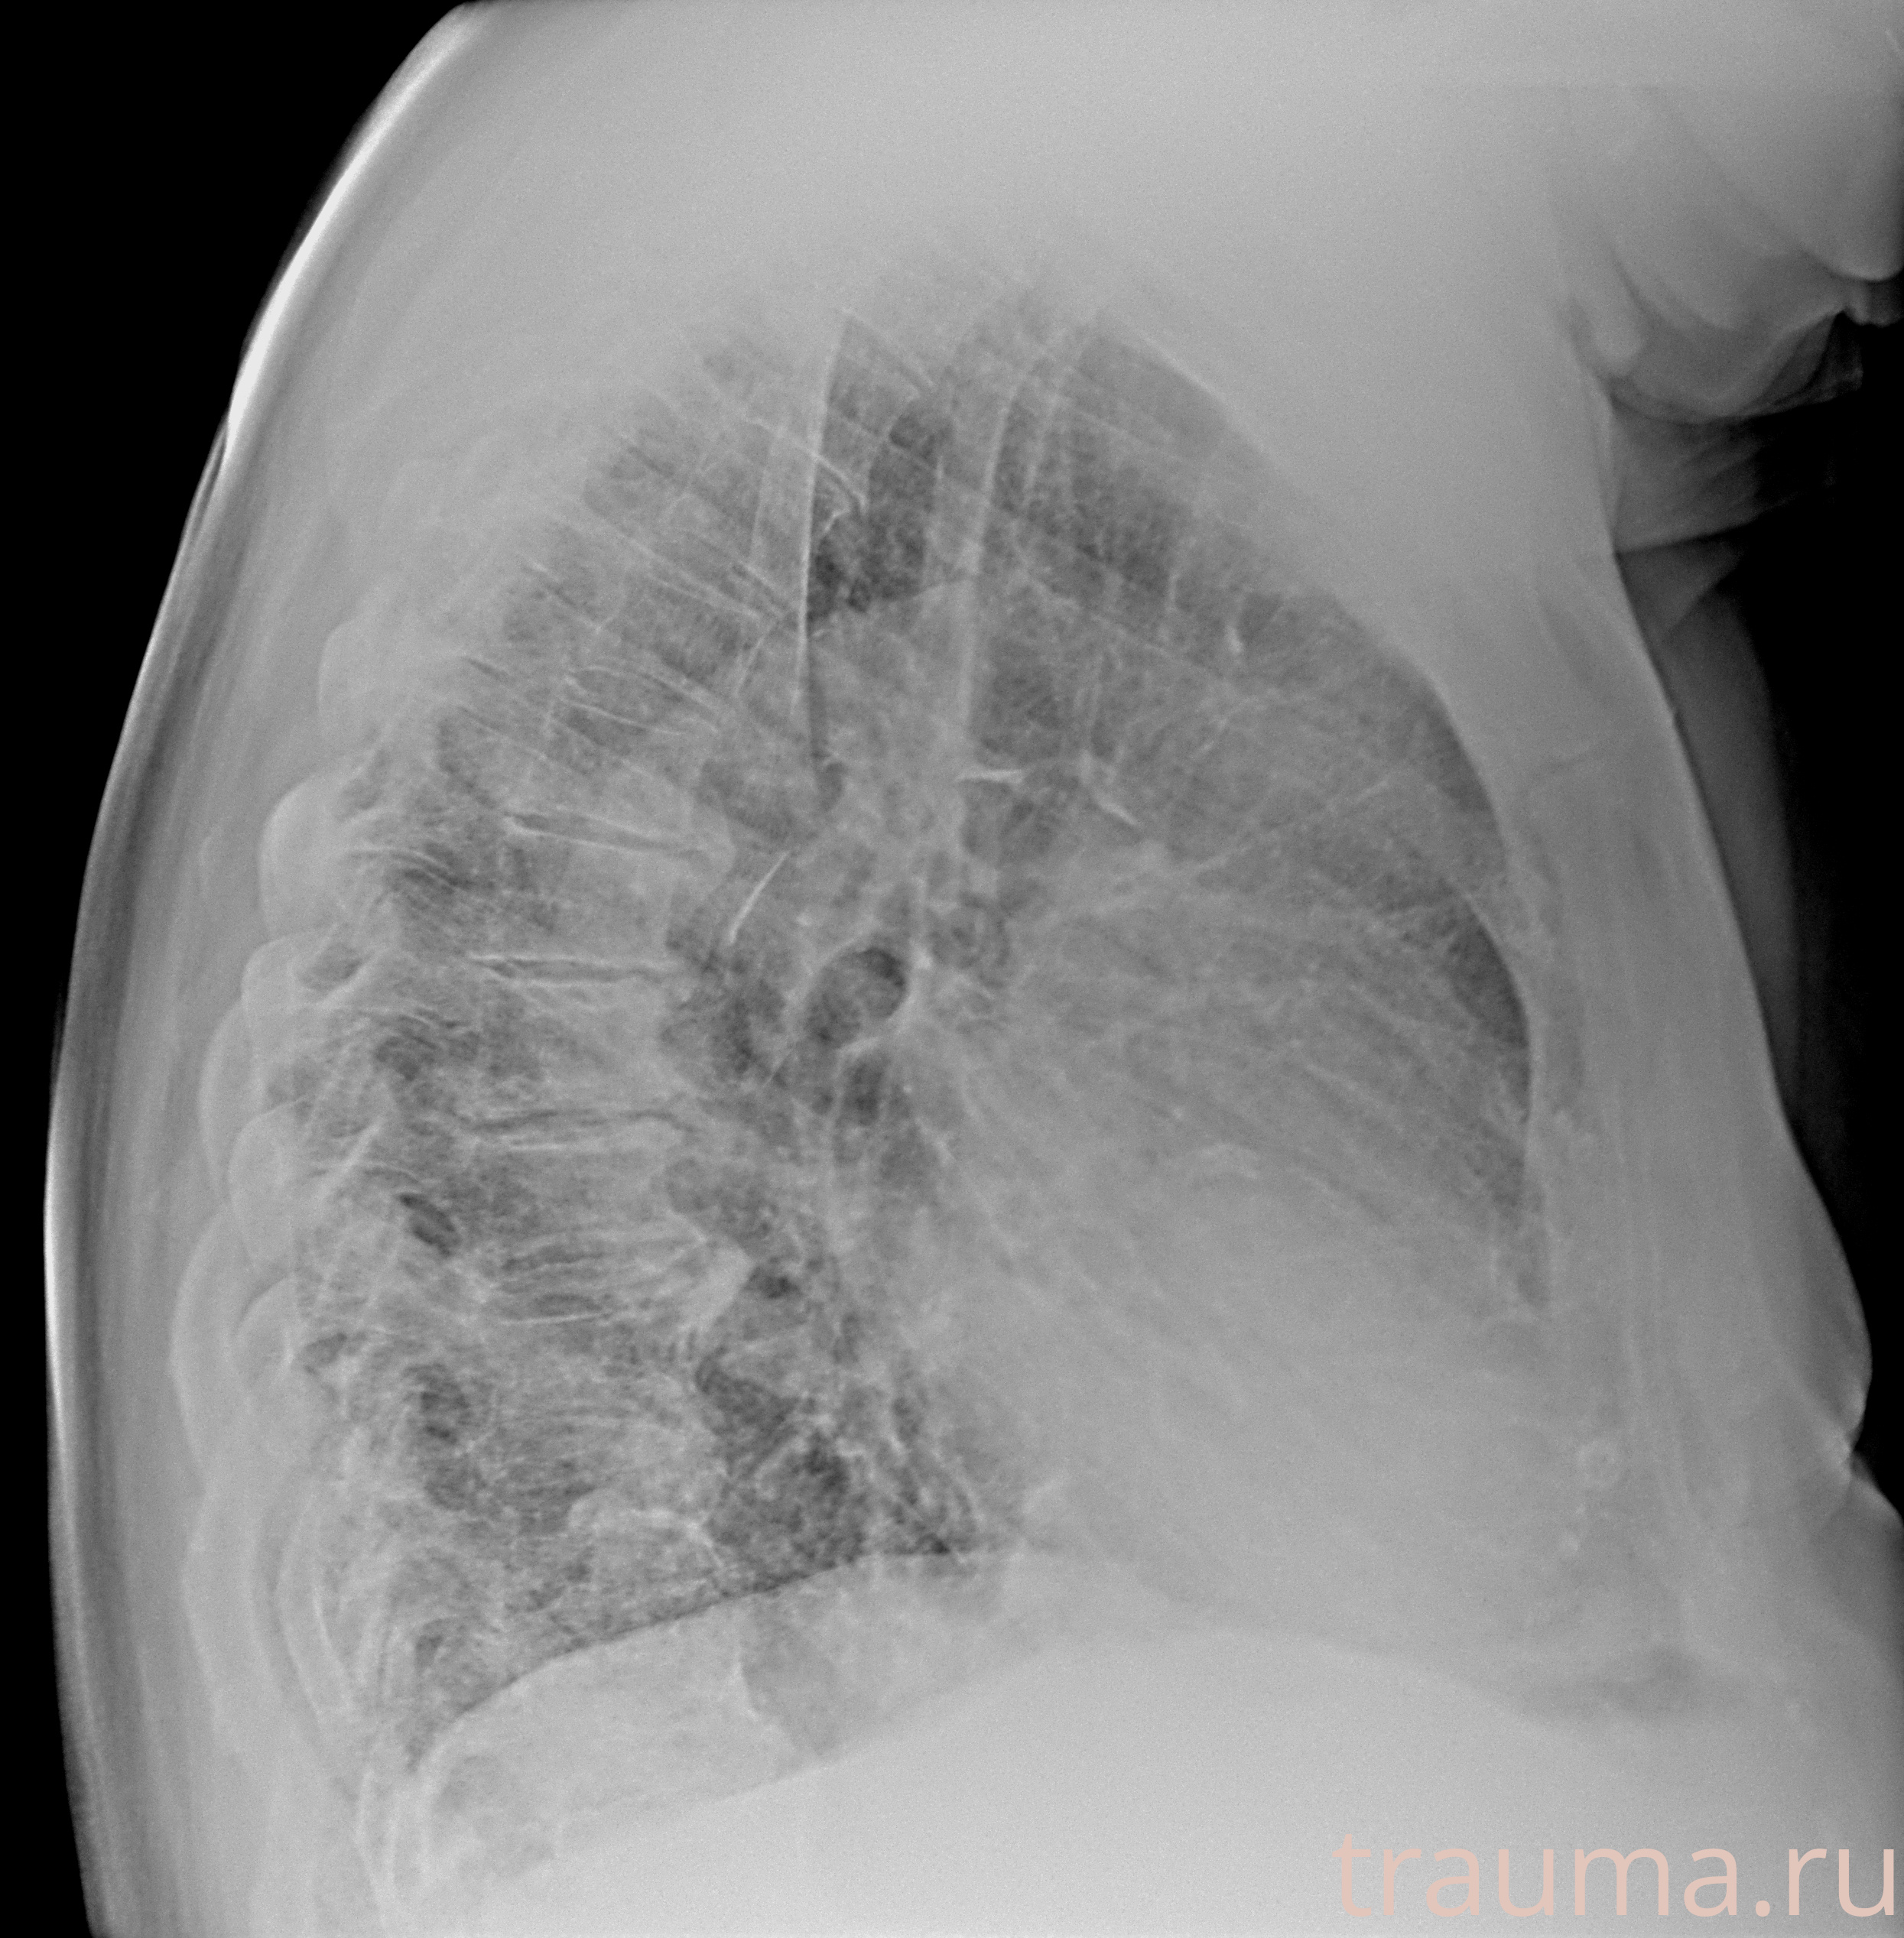

Рентгенограммы

Рентген на дому: по вашему адресу приезжает врач-рентгенолог, травматолог-ортопед с мобильным рентгеновским аппаратом, проводит диагностику травмы или заболевания, делает необходимые рентгенограммы, дает рекомендации по дальнейшему лечению. Получить качественные снимки в домашних условиях возможно благодаря уникальной методике, разработанной МосРентген Центром для института  Склифосовского

Яркость: 1   Контраст: 1   Инвертировать: 0 Увеличение: 1

Перетаскивайте мышь вверх/вниз для контраста, влево/право для яркости. Прокрутка колесом изменяет масштаб. Нажмите Сбросить для возврата к исходному изображению. При увеличении держите мышь в той области, которую хотите рассмотреть.